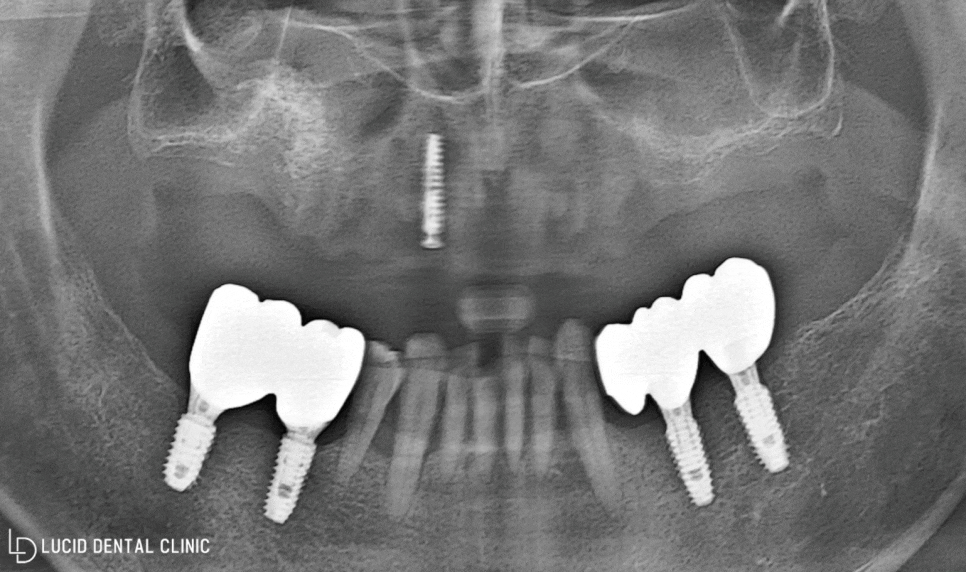

- 최종 종료

보다 빠르게 식립하고 치유할 수 있도록

가이드 보조 장치를 통해 진행했는데요

빠른 시간뿐만 아니라 통증 및 출혈을

최소화 할 수 있다는 장점이 있습니다.

아래 사진과 같이 임플란트 수술 을

안정적으로 마친 모습을 볼 수 있습니다.